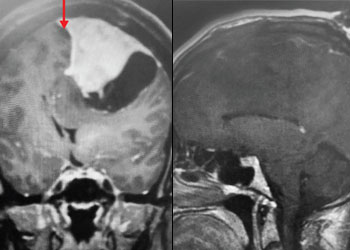

Below are the pre-operative MRI cervical spine images showing a left-sided C6/C7 herniated disc with pressure on the existing left C7 nerve root.